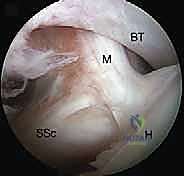

2. إحداث الثقوب (Portals) واستكشاف المفصل

يقوم الدكتور هطيف بعمل 3 إلى 4 ثقوب صغيرة جداً حول الكتف. يُدخل كاميرا المنظار (Arthroscope) لعمل جولة استكشافية شاملة لداخل المفصل، وتقييم الغضاريف، أوتار الكفة المد